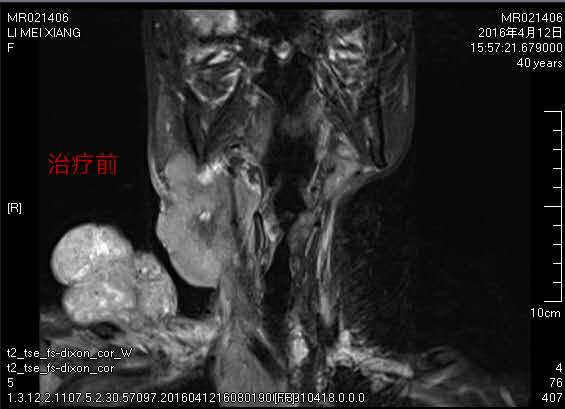

不屈服的她四處求醫(yī),經(jīng)過一年的時間,右頸部長出12cmX9cm的巨大腫塊,并向右肩部及上頜部蔓延,逐漸破潰流膿滲血,散發(fā)出陣陣惡臭。如果腫塊再進行性增大將直接壓迫氣管,危及生命,絕望的李大姐夜夜輾轉(zhuǎn)難眠。

第一次介入治療后,腫瘤就縮小了一半,出血也逐漸停止,頸部潰爛的皮膚逐漸好轉(zhuǎn),為接下來的局部放療創(chuàng)造了條件。為鞏固治療,李大姐一共接受了三個療程的微創(chuàng)介入灌注治療,目前右頸部巨大腫塊已基本消退。治療后身體日漸康復(fù)的李大姐對未來充滿了信心。